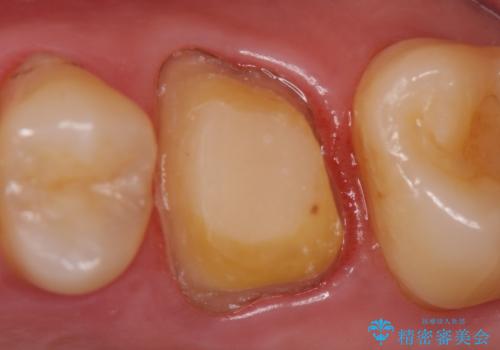

- ものを咬むと痛むので診て欲しいといらっしゃった方の症例です。

数年前に他院にて虫歯治療後しばらく痛みがあったが、やがて治まった。その後何事もなかったが、数か月前からものを咬むと痛むようになったとのこと。

検査の結果歯の神経が死んでいたため根管治療を施し、症状が治まったのを確認後オールセラミッククラウンによる補綴を行いました。